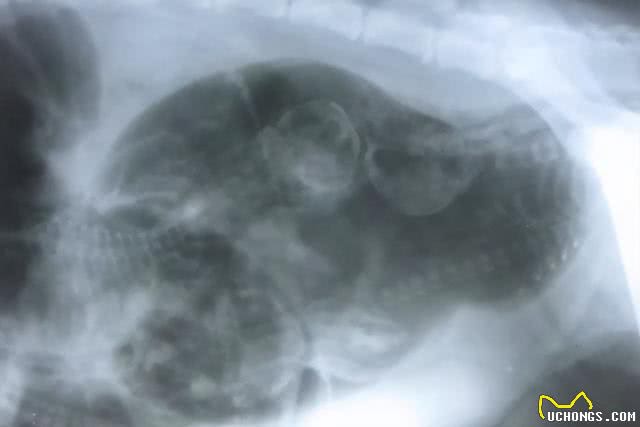

6.怀孕45天后,可以去医院做个B超,检查怀了几胎,这样如果在家生的话心里有数,不要太早去做B超或者X光,有导致宝宝畸形的风险。

当狗狗在怀孕55天(平均怀孕60天),时主人可以考虑带到宠物医院拍片最好拍DR(片子清楚很多)或者做B产,确定狗狗的个数,这样,在生小狗的时候心里有个底。怀孕55d以后就得评估狗狗的体胖了,怀孕期间并不是吃越多越好,合理的饮食量。可以很好的控制小狗的体型,防止因为狗妈妈吃太好,导致小狗过大造成难产。除了以上几个方面预防,适当运动是必须的。

假孕多发生在发情后2~3个月。母犬腹部增大,触诊腹壁可感觉子宫增厚,乳房发育膨胀,泌乳。母犬急躁,寻找黑暗的窝,喜欢喝水,食欲不振,有时还会出现呕吐、多尿等症状。根据配种史,腹部触诊, X线摄影和超声诊断可以通过排除真正的酌情怀孕来确定。